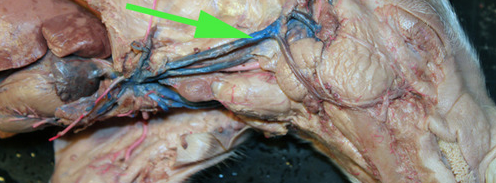

The vein marked by the green arrow is a renal vein

The vessel marked by the green arrow is a renal

artery.